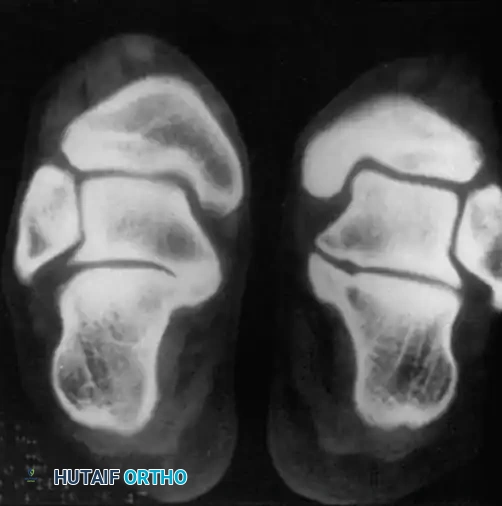

Fig. 1: CT scan demonstrating a medial facet tarsal coalition of the calcaneus and talus in a young patient presenting with frequent, recalcitrant ankle sprains.

Tarsal Coalitions

Tarsal coalitions, particularly talocalcaneal (medial facet) and calcaneonavicular coalitions, alter the kinematics of the hindfoot, leading to increased stress on the ankle joint. Adolescents with tarsal coalitions exhibit a statistically significant increase in the frequency of ankle sprains. Peroneal spastic flatfoot is a classic, though not universally present, clinical sign. Computed Tomography (CT) remains the gold standard for determining the exact anatomical location, osseous maturity, and extent of the coalition.